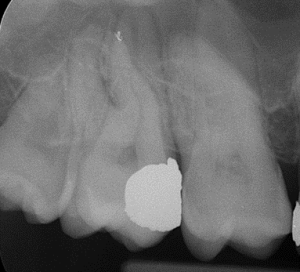

Apical Microsurgery / Apicectomy

Clinical Cases